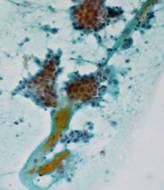

ローピーコロイドによる組織推定

ローピーコロイド ⇒ 乳頭増殖部鋳型 ⇒ 乳頭癌